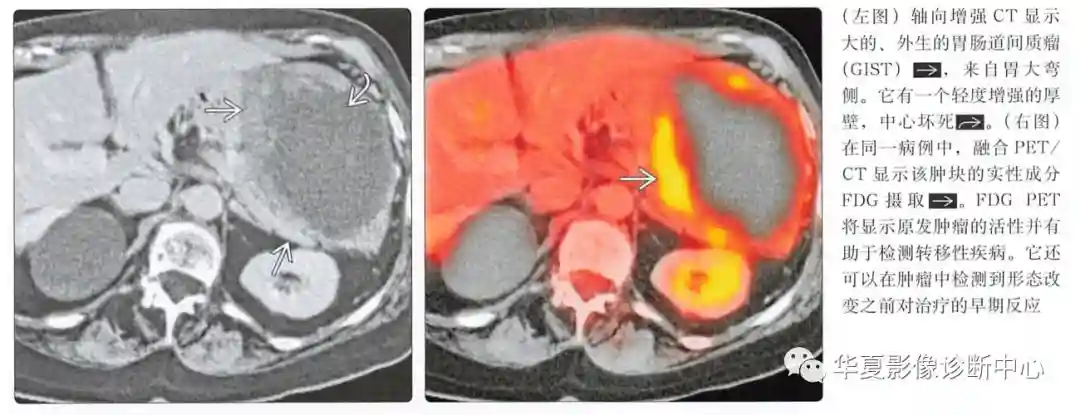

增强CT

动脉期图像呈低或高血供,边界清楚的黏膜下肿块;溃疡和坏死是常见的

核医学表现

PET

预测对伊马替尼(格列卫)的早期反应优于CT

高代谢(FDG-摄取)病灶提示存活肿瘤

原发性肿瘤和转移瘤均为高代谢